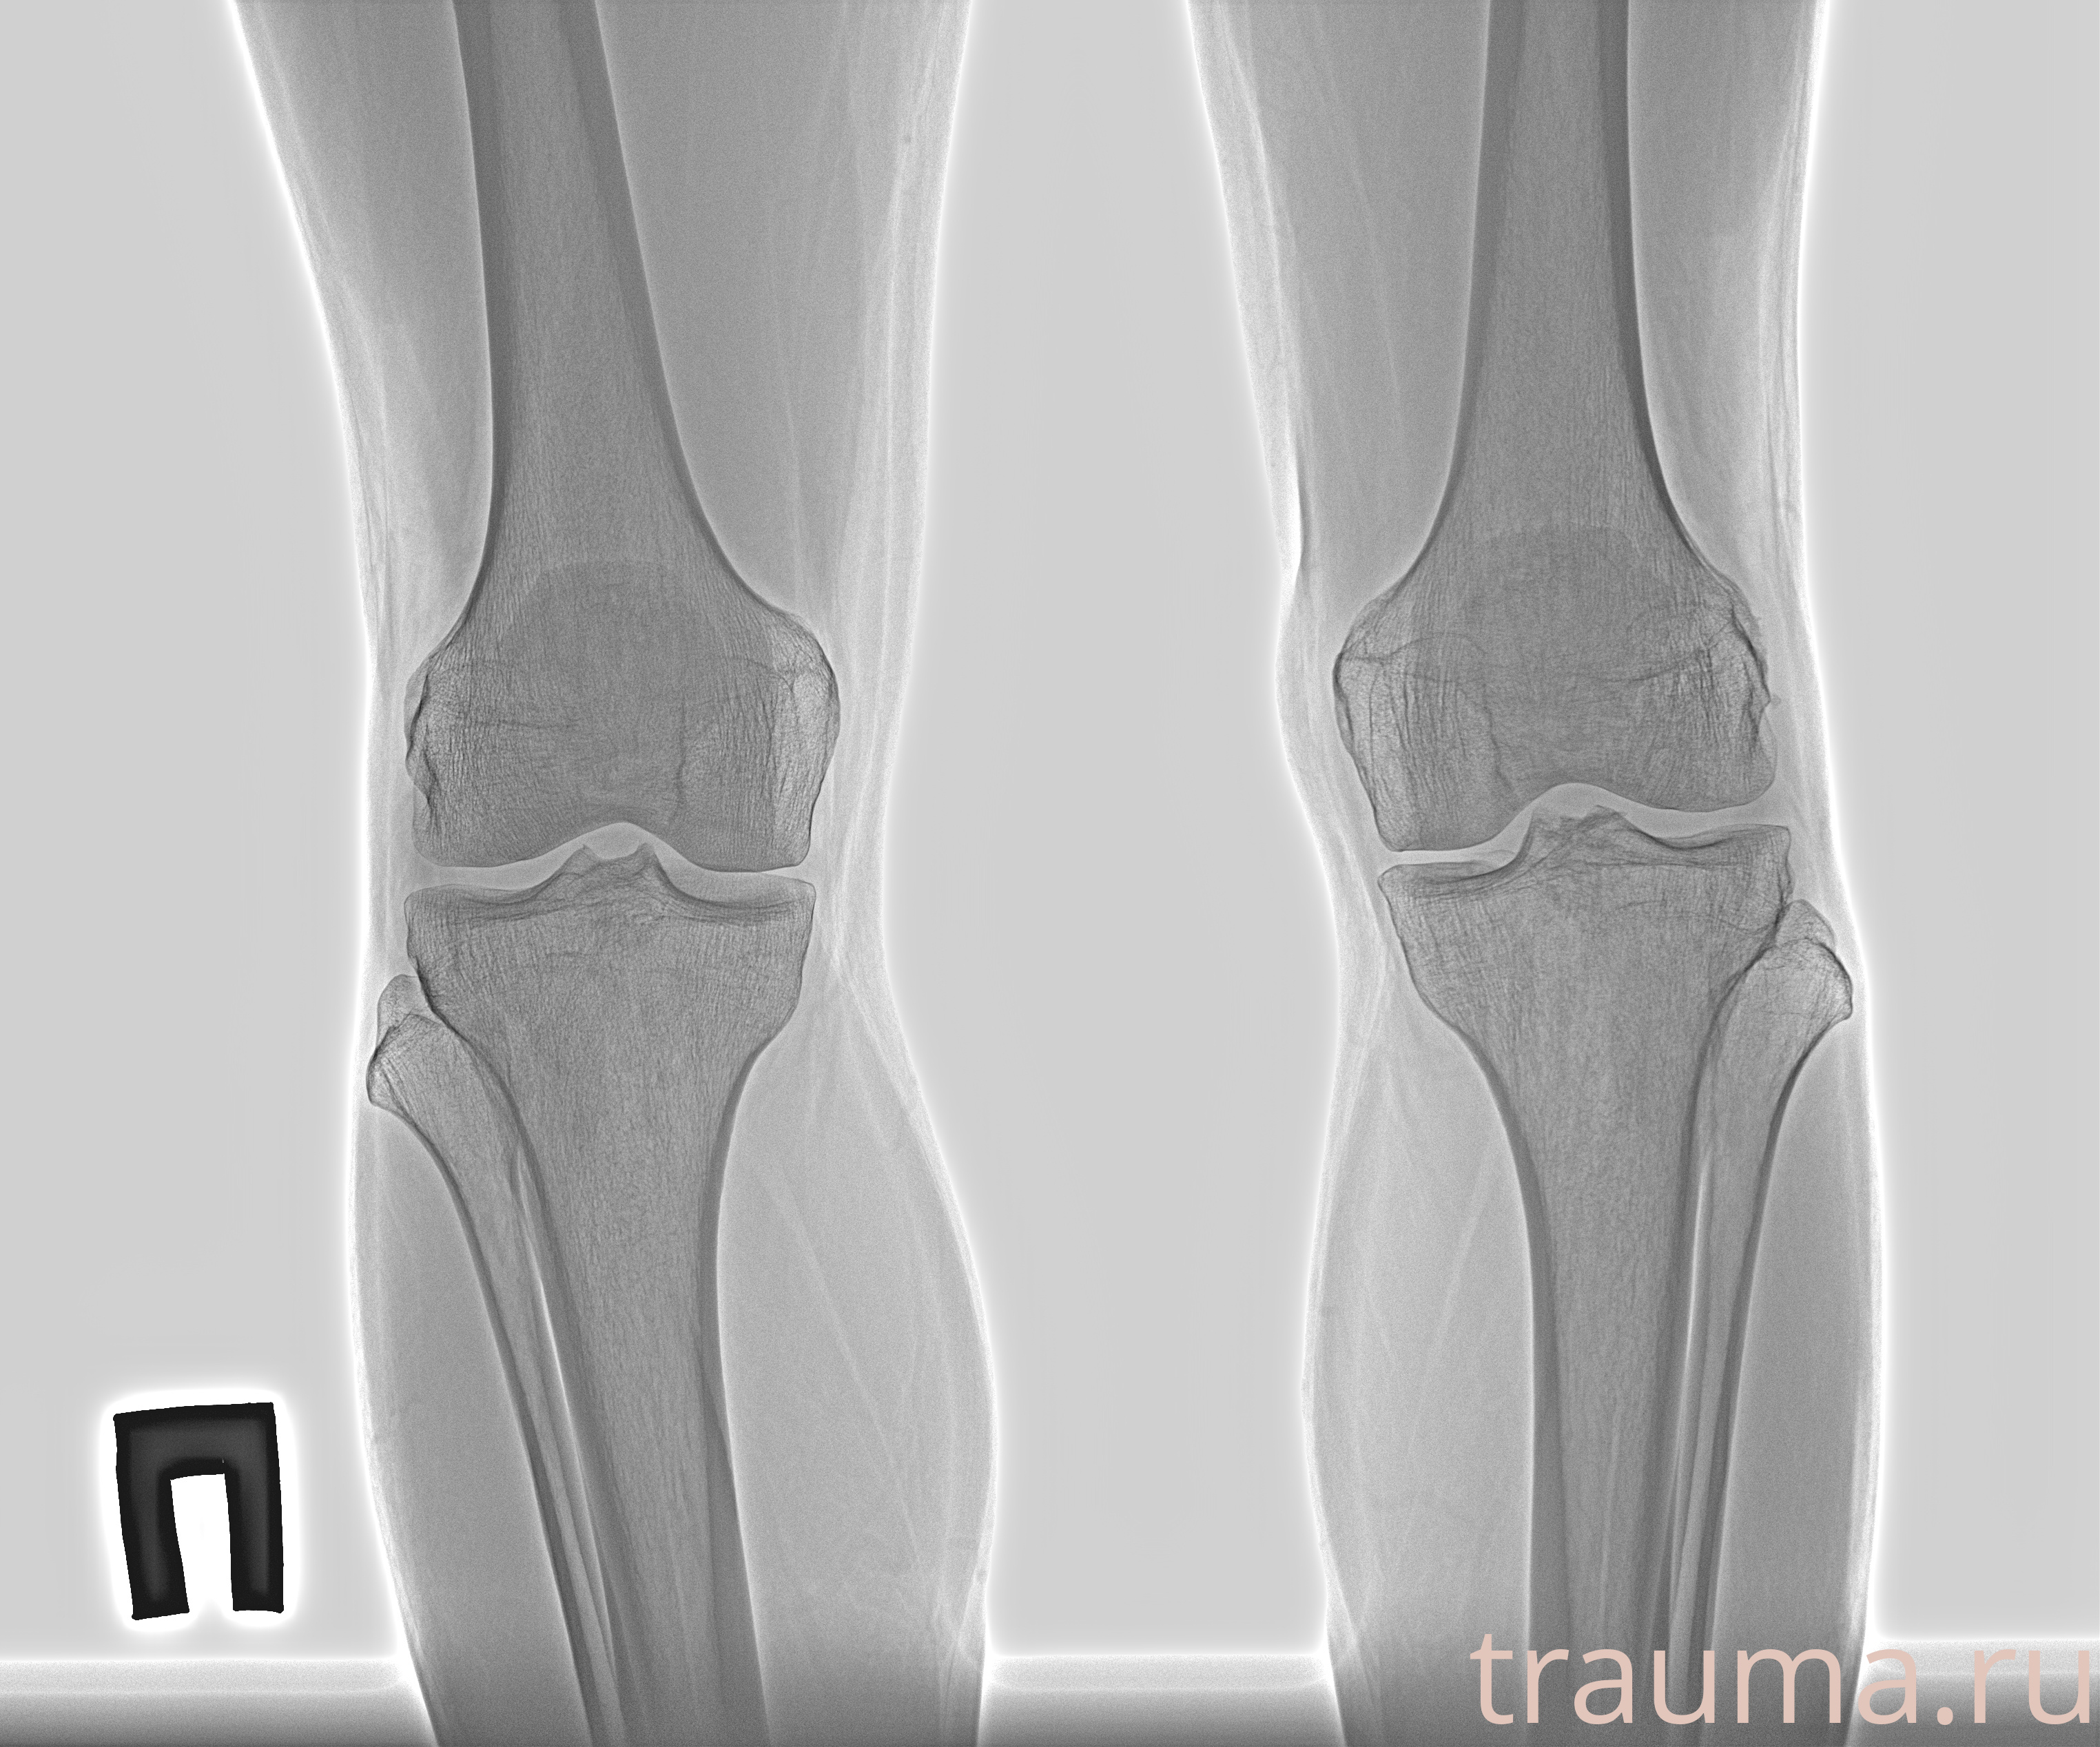

Рентген на дому: по вашему адресу приезжает врач-рентгенолог, травматолог-ортопед с мобильным рентгеновским аппаратом, проводит диагностику травмы или заболевания, делает необходимые рентгенограммы, дает рекомендации по дальнейшему лечению. Получить качественные снимки в домашних условиях возможно благодаря уникальной методике, разработанной МосРентген Центром для института  Склифосовского